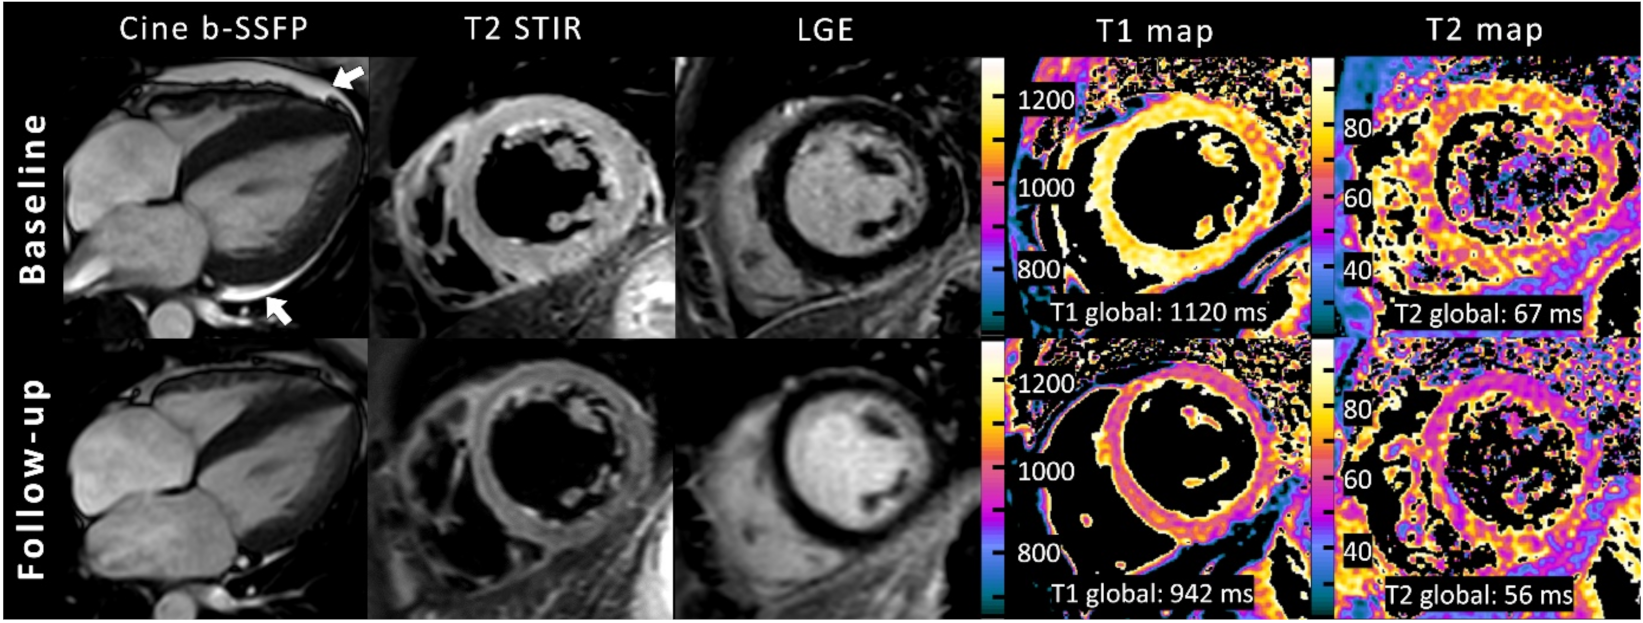

| Variable | Baseline (n = 6) | Follow-Up (n = 6) | p-Value |

|---|---|---|---|

| Left ventricular ejection fraction (%) | 38 ± 9 | 55 ± 17 | 0.011 |

| Left ventricular end-diastolic volume index (mL/m²) | 89 ± 28 | 85 ± 27 | 0.651 |

| Right ventricular ejection fraction (%) | 40 ± 18 | 55 ± 11 | 0.023 |

| Right ventricular end-diastolic volume index (mL/m²) | 66 ± 13 | 71 ± 15 | 0.370 |

| Left atrium volume index (mL/m²) | 56 ± 18 | 42 ± 10 | 0.051 |

| Left ventricular mass index (g/m²) | 61 ± 14 | 52 ± 8 | 0.176 |

| Interventricular septal thickness (mm) | 10 ± 2.8 | 9.1 ± 2.0 | 0.047 |

| T2 signal intensity ratio | 2.1 ± 0.3 | 1.7 ± 0.3 | 0.126 |

| Visual myocardial edema | 3 (50%) | 0 (0%) | 0.25 |

| Visual late gadolinium enhancement | 1 (20%) | 0 (0%) | 0.99 |

| Late gadolinium enhancement (%) | 4.5 ± 3.3 | 5.0 ± 2.6 | 0.363 |

| Global longitudinal strain (%) | −13.5 ± 4.8 | −19.8 ± 5.8 | 0.039 |

| Global circumferential strain (%) | −15.6 ± 8.1 | −18.7 ± 9.5 | 0.009 |

| Global radial strain (%) | 30.1 ± 21.9 | 30.5 ± 17.6 | 0.935 |